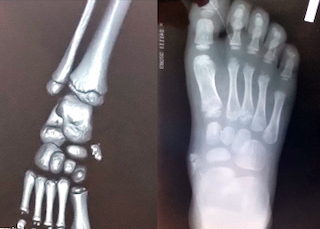

Рентгенография. Это первое и основное инструментальное исследование. На рентгенограмме гигантоклеточная опухоль кости обычно выглядит как литический очаг (область разрушения кости) с чёткими, но не всегда склерозированными краями. Может быть виден истончённый кортикальный слой кости или вздутие кости. Рентгенография позволяет заподозрить ГКОК и определить её приблизительные размеры и локализацию.